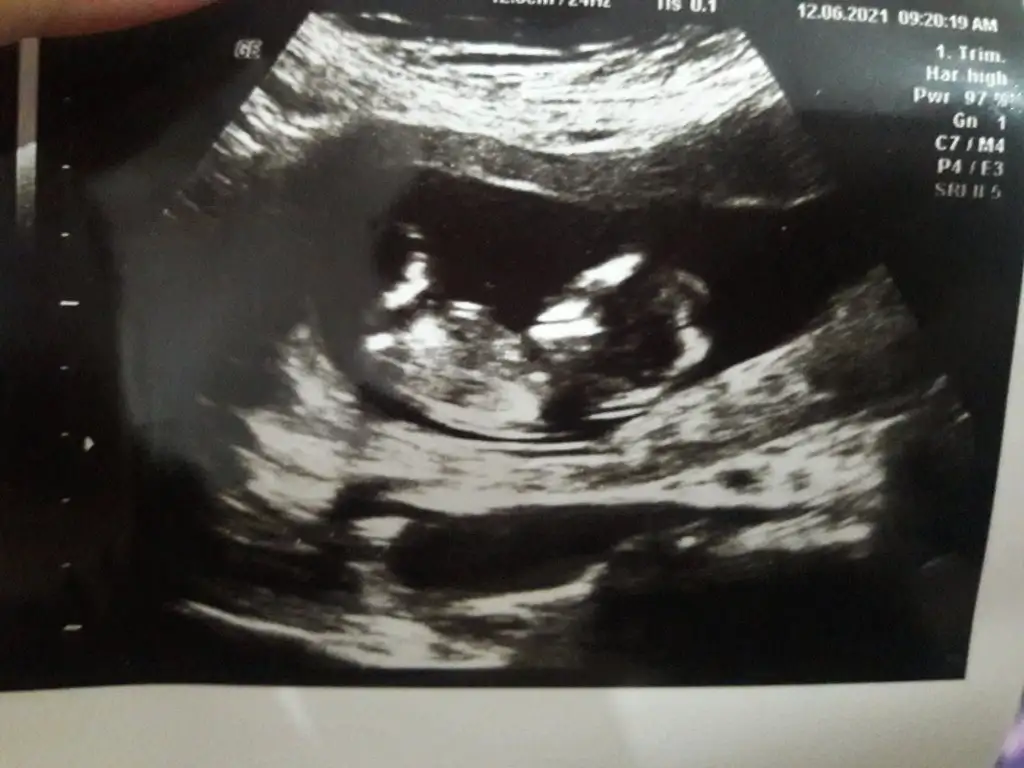

Kız görünüyorEki Görüntüle 2870138 11+5 teyim. Tahmin eder misiniz

Ikra meyra canim bana dün yorum yapmıştın ama herkes farklı söylüyor. Rica etsem tekrar bakabilir misin.(12+5) Şimdiden çok teşekkür ederim..